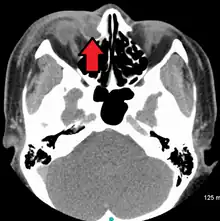

A case of dacryocystitis as seen on CT scan | |

Dacryocystitis is an infection of the lacrimal sac, secondary to obstruction of the nasolacrimal duct at the junction of lacrimal sac.[1] The term derives from the Greek dákryon (tear),[2] cysta (sac), and -itis (inflammation). It causes pain, redness, and swelling over the inner aspect of the lower eyelid and epiphora. When nasolacrimal duct obstruction is secondary to a congenital barrier it is referred to as dacryocystocele. It is most commonly caused by Staphylococcus aureus and Streptococcus pneumoniae.[3] The most common complication is corneal ulceration, frequently in association with S. pneumoniae.[3] The mainstays of treatment are oral antibiotics, warm compresses, and relief of nasolacrimal duct obstruction by dacryocystorhinostomy.[3]